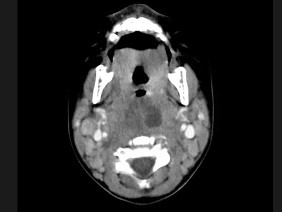

18.10個(gè)月大的嬰兒,發(fā)熱,曾患中耳炎,CT掃描如圖所示,請(qǐng)選擇正確的描述或診斷  (    )

正確答案:ABCD